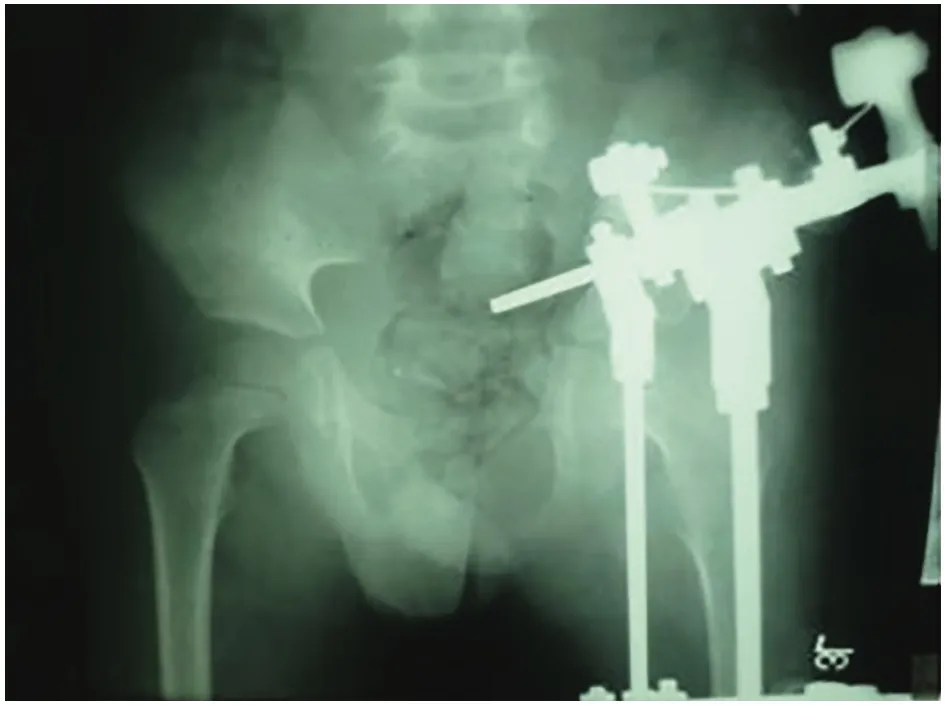

Osteotomy means making a controlled cut in the bone to allow correction. In Ilizarov Hip Reconstruction, the surgeon carefully cuts the femur or pelvis so the external fixator can gradually realign the hip. This process allows bone healing while correcting deformities or leg length differences.

The Ilizarov technique uses a circular external fixator that applies gentle, controlled tension to bones. This stimulates natural bone regeneration (distraction osteogenesis), which allows bones to grow in length and correct deformities. It is widely used for hip, leg, and complex orthopedic reconstructions.